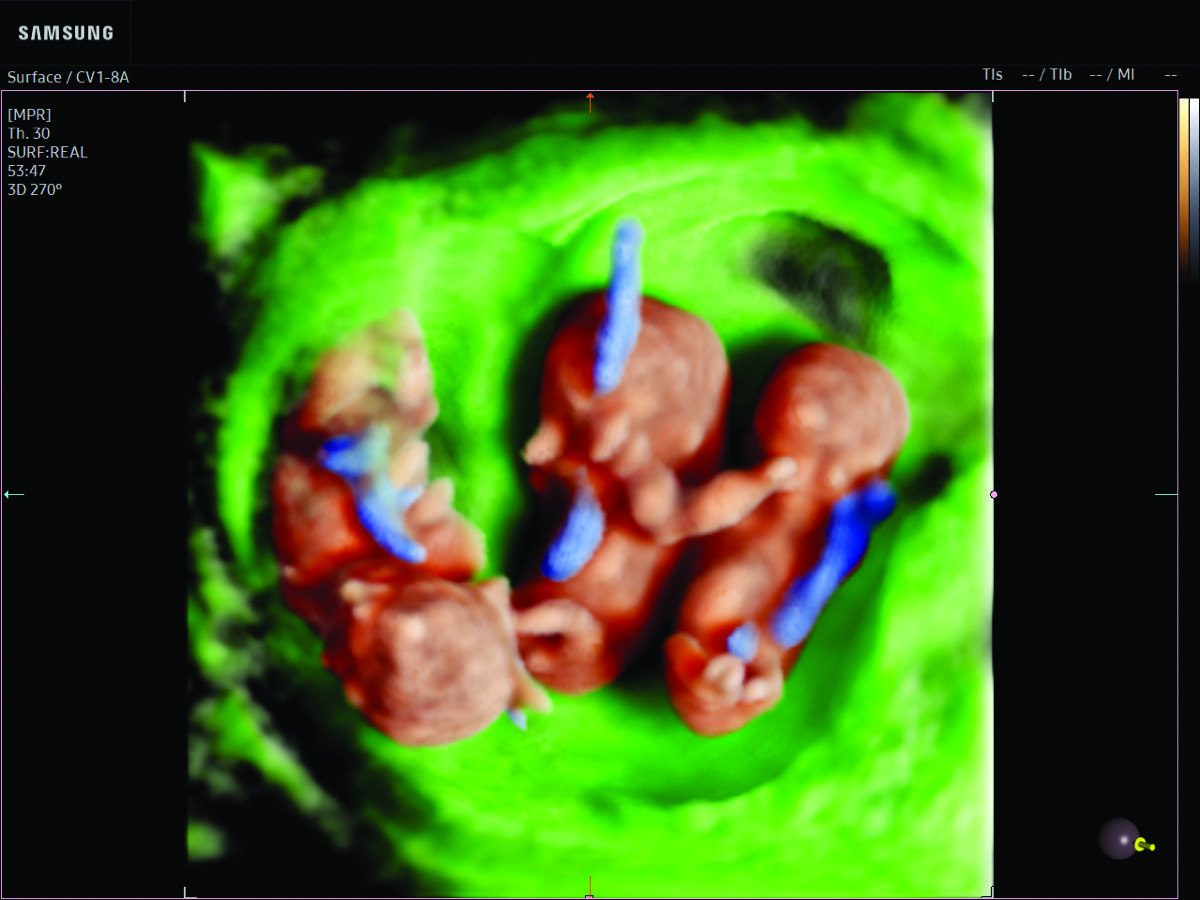

Comprehensive, advanced and expert MFM care for high-risk pregnancies

- Multiple births

- Fetal anomalies